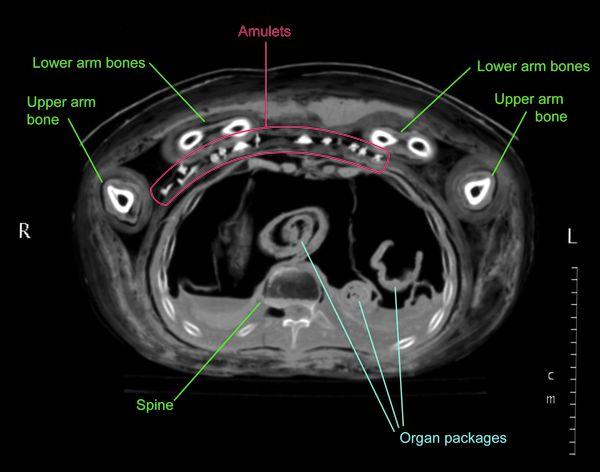

Medical imaging technology and software have advanced so much over the last fifteen years that new reconstructions from the 2011 CT scan data show Nesmin's body and these small amulets (about 1–1 1/2 in.) with astonishing clarity (see figs. 11–12, and especially 14 and 16).

Older X-rays and CT scans of Nesmin that were taken in 1995 and 1997 (figs. 7–8, 10, and 13)2 had shown that his mummy is accompanied by a very large set of amulets (thirty-one in total) within the wrappings. The images that were produced at the time were on film and allowed the identification of the types of amulets (such as a standing god), but the information from these old images was limited and the visible details were not sufficient to permit the identification of the particular gods included, for example.

Radiographic analysis can not only detect objects within the wrappings, but it can also provide information about mummification techniques or the health of an individual. In Nesmin's case we can, for example, see that most of his organs were removed, mummified separately, and then placed back into the chest and stomach cavity (see fig. 8); this was a common practice in the Ptolemaic Period. Images of his hips revealed that he suffered from arthritis.3